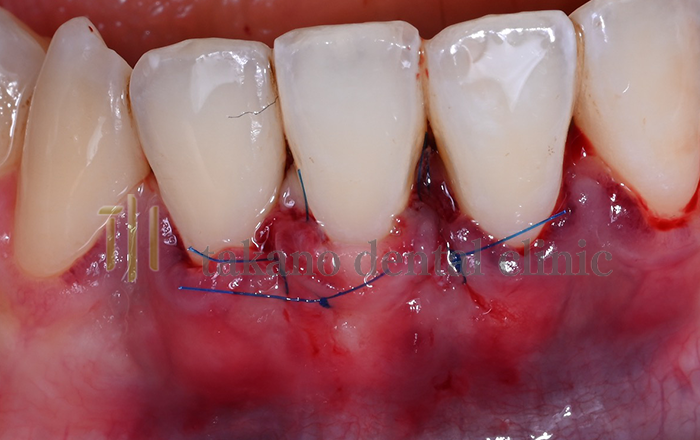

下がった歯ぐきを治療するためには歯周形成外科治療が必要になります下がった歯ぐきを治療するためには歯周形成外科治療が必要になります。外科治療には遊離歯肉移植術、結合組織移植術、歯肉弁歯冠側移動術といった手術をおこないます。

結合組織移植術

case01

• 術前

治療例

• 術中

• 術後